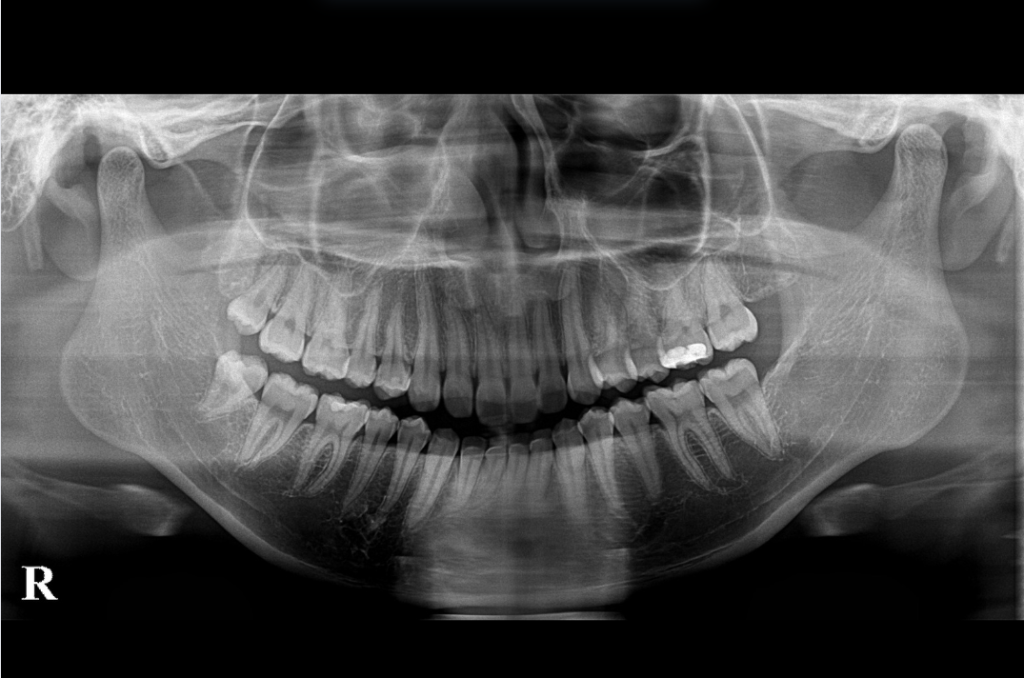

さらに、1~2年に1回程度のパノラマレントゲン撮影もおすすめです。目に見えない部分のむし歯や、歯周病による骨の状態、親知らずの位置などを確認できるため、トラブルの早期発見に大きく役立ちます。自覚症状がなくても隠れた異常を見つけられる点で、とても重要な検査です。